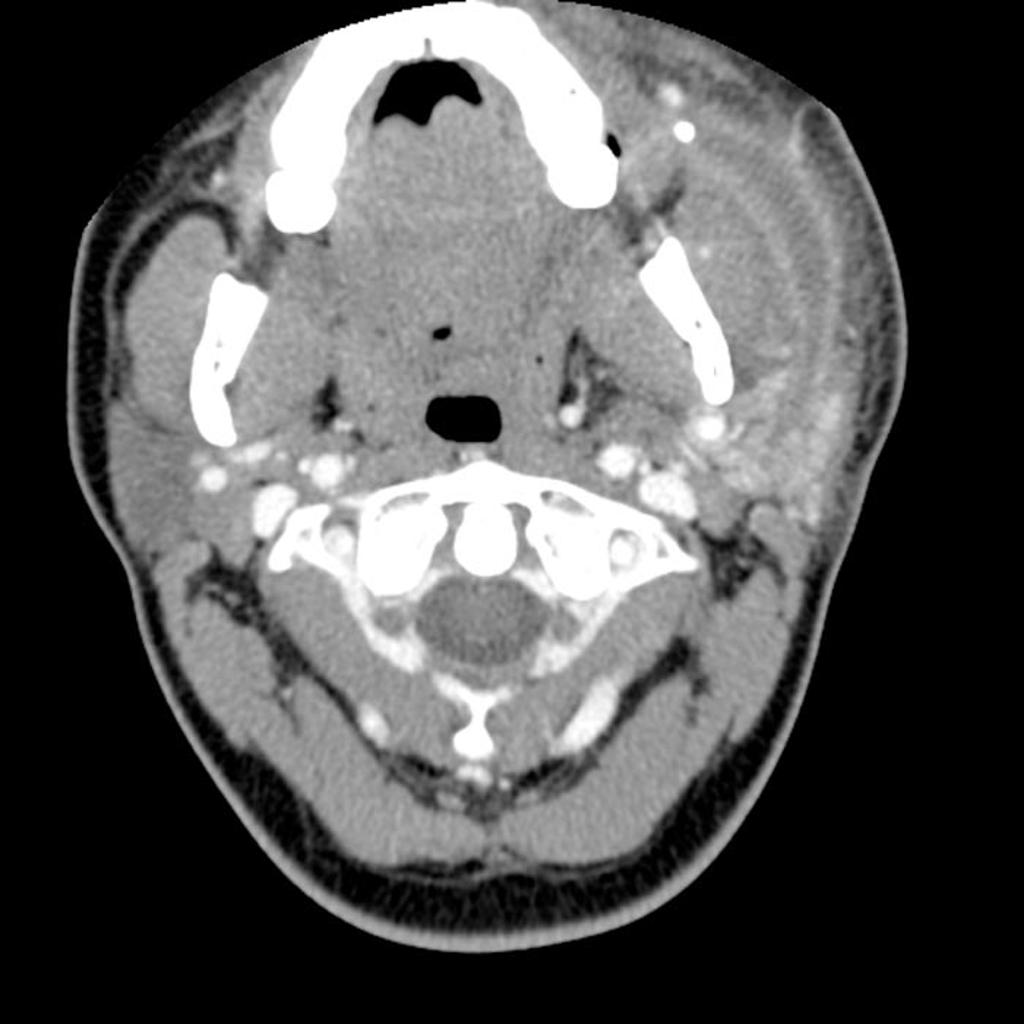

We have three main salivary glands on each side of the face: the parotid gland, the submandibular gland, and the sublingual gland. There are also several hundred tiny accessory salivary glands located beneath the mucosal lining of the mouth, including the palate, lips, and pharynx.

The parotid gland is the largest of the salivary glands. It is located below and in front of the ear, in the angle of the jaw. Its role, like that of the other salivary glands, is to produce and secrete saliva, thereby facilitating chewing and swallowing.